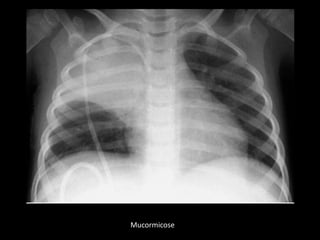

Mucormicose